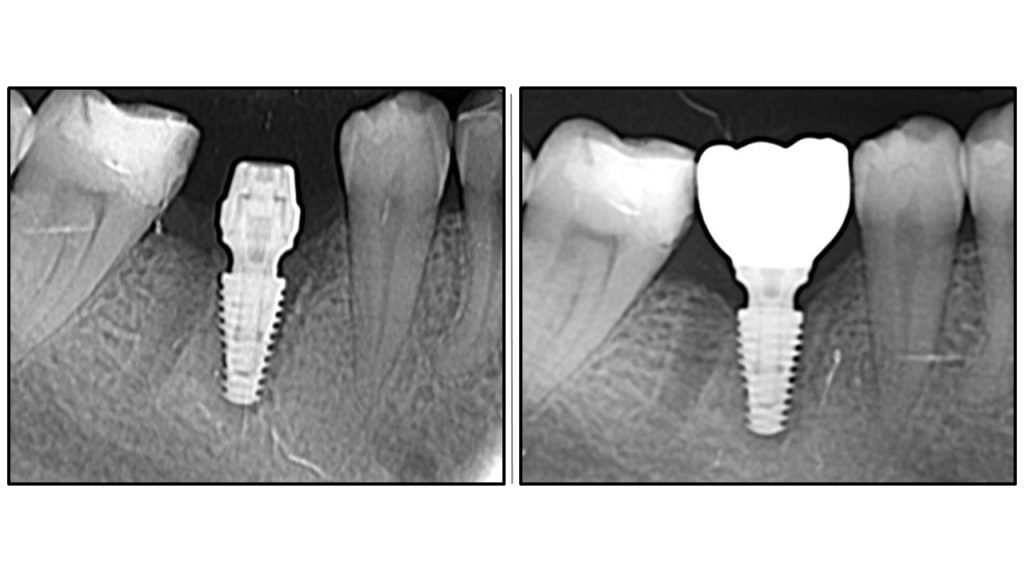

Radiographic Analysis: Crestal Bone Stability

Comparative radiographic study of crestal bone stability: OAOT protocol. Postoperative radiography vs. Final prosthetics.

The first image showing postoperative radiography and the second final ceramic crown

Bone remodelling

Bone remodelling around implant abutment connection is flawless

Stable peri implant tissue

No bone recession is visible

OAOT protocol - superior results.

Another example of One Abutment One Time protocol